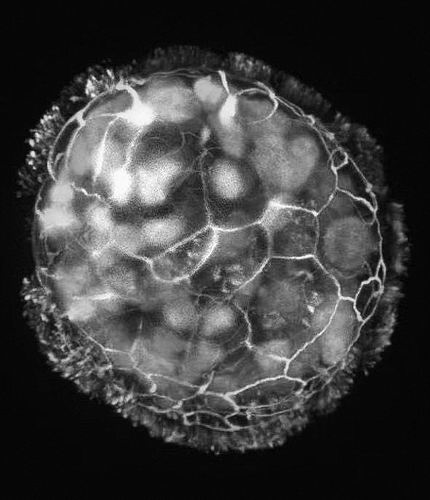

莱文和他的团队在凝胶中培养了人类气管皮肤细胞的球状体两周,然后将这些细胞团移走,在粘度较低的溶液中培养一周。这导致细胞上称为纤毛的微小毛发移动到球状体外部而不是内部。研究人员发现,由此产生的每个“Anthrobots”都含有几百个细胞,它们经常以几种模式中的一种游动,有的呈直线游动,有的按照圆圈或弧线的轨迹游动,有的则混乱地移动。

为了测试这些“Anthrobots”的治疗潜力,莱文和他的同事们将几个“Anthrobots”放在一个小盘子里。在那里,这些“机器人”融合在一起,形成了一个“超级机器人”(superobot),研究人员将其放置在被划伤的神经组织的表层。三天之内,受损的神经元完全愈合。